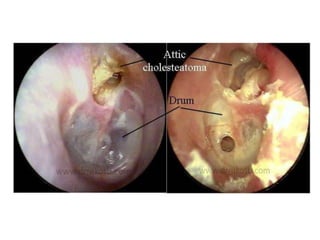

1. Cholesteatoma.

1. Perforation.

It is either attic or postero-superior marginal

type.

3. Cholesteatoma.

• It is the presence of keratinizing squamous epithelium in

the middle ear or mastoid.

• “Skin in the wrong place.”

• Essentially, cholesteatoma consists of two parts:

(i) the matrix, which is made up of keratinizing squamous

epithelium resting on a thin stroma of fibrous tissues and

(ii) a central white mass, consisting of keratin debris

produced by the matrix .